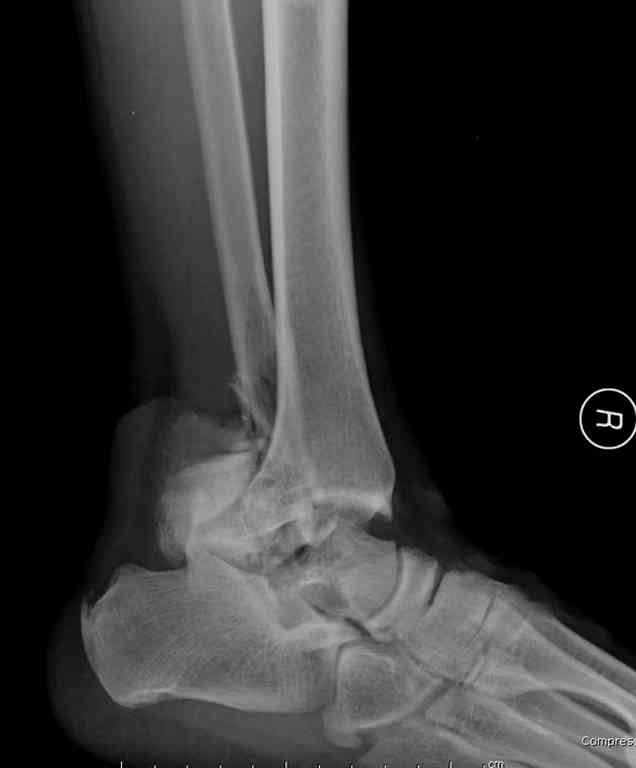

Прошу коллег помочь советом.3 дня назад поступила пациентка 23 года с переломом шейки ладьевидной справа, переломом лодыжек и заднего края б/берцовой кости со смещением и подвывихом кзади, переломом внутреннего мыщелка правого бедра без смещения. Дежурными хирургами проведена репозиция в левом г/ст суставе успешная, попытка репозиции таранной кости ухудшило положение отломков. Планируем провести повторную репозицию и фиксацию винтами. 1. Закрытая репозиция рентгенконтоль интраоперационный (аппарат Арман) ификсация из заднее-наружного доступа. 2. При неудачной закрытой репозиции переходим на открытое вправление двумя доступами медиальным и латеральным "по ходу оси таранной кости" и через дополнительный задний доступ вводим винты кортикальные 4,5 мм или 3,5 мм 3. после открытой репозиции фиксация двумя винтами через боковые доступы погружая их под суставную поверхность Сергей Зырянов ЦРБ Новосибирская область

z> 3 дня назад поступила пациентка 23 года с переломом шейки ладьевидной

z> справа, переломом лодыжек заднего края б/берцовой кости со смещением и

z> подвывихом кзади, переломом внутреннего мыщелка правого бедра без смещения.

Это на той же ноге, где таран, или нет? Если нет, эти сведения вряд ли влияют на планирование в отношении обсуждаемой таранной кости.

z> Планируем провести повторную репозицию и фиксацию винтами.

Есть смысл подумать не только о репозиции и остеосинтезе тарана (попытка сделать это закрыто без ЭОП, по-моему, неоправдана), но и об артродезе подтаранного сустава. Он поврежден уже, т.е. ожидаем артроз. Плюс кровоснабжение аваскулярного блока таранной кости будет

обеспечиваться со стороны пятки. Это ускорит реваскуяризацию блока тарана. Достаточно одного наружного доступа.

Уважаемый Сергей

В данном случае вероятность аваскулярного некроза очень высока, но пациентка молодая и нельзя лишать её шанса на сращение перелома. Нет ни

какого сомнения что необходимо выполнить открытую репозицию. Для выполнения качественной репозиции необходим визуальный контроль, ЭОП не достаточно.

Обычно используется доступ с остетомией внутренней лодыжки, но у вашей пациентки есть перелом лодыжки что можно использовать для доступа к таранной кости и в конце операции зафиксировать перелом лодыжки. К сожалению нет

переднезаднего снимка, так что через какую лодыжку идти не могу сказать.

Канулированные винты могут вам очень помочь.